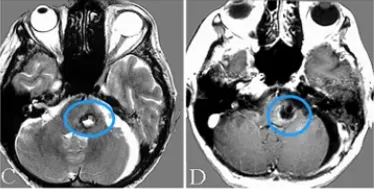

65岁女士,有左侧面部神经瘫痪和头晕1月,随后出现吞咽障碍和声带麻痹,影像检查显示3厘米大小的占位,考虑主要是血栓形成的VA椎动脉瘤,包括PICA(图1)。巴特朗菲教授为其进行血管搭桥术,术后动脉瘤血栓形成的部分几乎完全切除,无因手术造成的神经功能缺损。

图1A-C:术前磁共振扫描显示部分血栓形成的VA-PICA动脉瘤,并压迫脑干。

图1D:术前左侧VA造影显示大量血栓形成的VA-PICA动脉瘤的灌注部分(箭头);图1E:术前左侧VA血管造影,VA-PICA动脉瘤合并巨大血栓形成,显示动脉瘤灌注部分(星形)和不同直径的左侧VA(箭头)和PICA(双箭头);图1F:磁共振血管造影显示VA-PICA动脉瘤部分血栓形成(箭头)。

图1G:CT显示动脉瘤的血栓形成及部分钙化。

术后情况:病人在手术当天即神志清楚,没有出现新发的神经功能缺损。在术后第一天的检查中,未发现局部或远端梗死和吻合口再出血(图2A-B)。MR显示脑干压迫效应解除(图2C-和D),术后血管造影显示吻合的PICA充盈良好、血流通畅(图2E-F)。术后恢复顺利,无术后并发症。经过7年的随访,声带麻痹已痊愈,生活正常。

图2C-D:术后MR显示动脉瘤体切除。